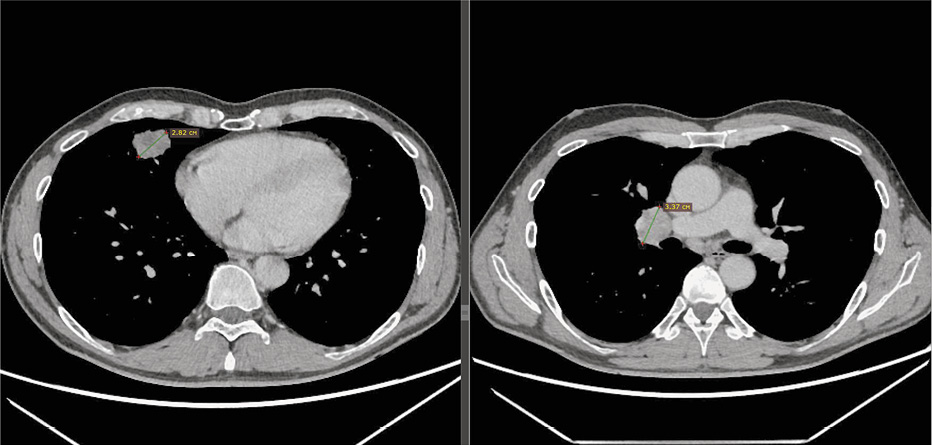

В табл. 1 мы также приводим один из клинических случаев с метастатическим поражением костей (случай 5). Диагноз был впервые поставлен в 2013 г. – аденокарцинома правого легкого, стадия I (Т1N0М0) – проведена верхняя лобэктомия. В сентябре 2019 г. зарегистрирован рецидив заболевания: метастазы в легкие, лимфатические узлы средостения, позвоночник. С октября 2019 г. пациентке был назначен осимертиниб, проводилось лечение деносумабом в течение 9 мес. В сентябре 2020 г. была проведена дистанционная лучевая терапия на область ThXII–LI (СОД=24 Гр). По данным первой контрольной компьютерной томографии после начала терапии осимертинибом – исчезновение очагов в легких, положительная динамика в отношении лимфатических узлов средостения. По данным однофотонной эмиссионной компьютерной томографии отмечается положительная динамика за счет уменьшения числа, размеров и снижения метаболической активности в ранее выявленных очагах поражения костной системы. Пациентка продолжает терапию осимертинибом уже более 2 лет (рис. 5).

Рис. 5. Пациент 5. Однофотонная эмиссионная компьютерная томография: a – от 17.10.19 – до начала лечения; b – снимки на фоне терапии осимертинибом от октября и марта 2021 г.

Fig. 5. Patient 5. Single-photon emission computed tomography: a – 17.10.19 – before the beginning of the treatment; b – images against the background of osimertinib therapy, October and March 2021.